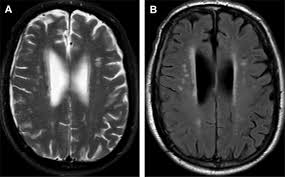

In this study, the researchers examined whether epigenetic measures of biological aging are associated with structural brain changes linked to aging and Alzheimer’s disease. Using data from 1,196 older women enrolled in the Women’s Health Initiative Memory Study, they analyzed five widely used epigenetic clocks and compared them with MRI-derived measures obtained approximately eight years later.

The findings revealed a clear distinction between different aspects of aging. None of the epigenetic clocks were associated with accelerated brain aging as measured by the SPARE-BA index, a composite MRI marker of brain age. However, one specific clock—AgeAccelGrim2—was significantly associated with the Alzheimer’s Disease Pattern Similarity Score (AD-PS), a validated imaging biomarker linked to increased risk of dementia.

Further analyses suggested that this association was largely driven by epigenetic signatures related to smoking exposure. In particular, a DNA methylation marker reflecting cumulative smoking history was linked to reduced frontal and temporal lobe volumes—regions commonly affected in age-related neurodegeneration. Notably, no significant associations were observed with hippocampal or entorhinal cortex volumes, areas more directly implicated in early Alzheimer’s pathology.